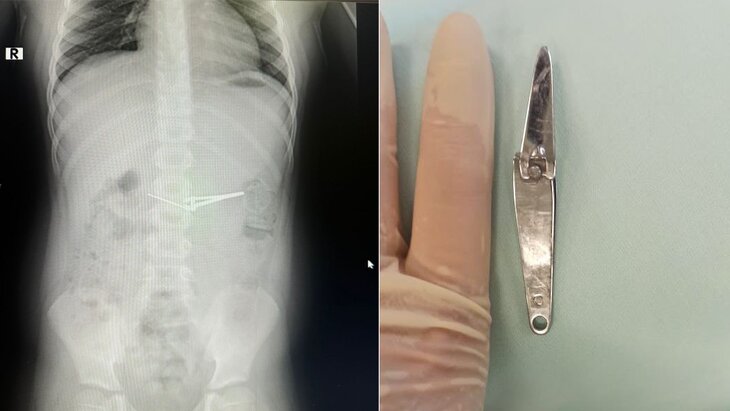

Фото: телеграм-канал "Минздрав Башкортостана"

Шестилетний мальчик, проглотивший щипцы для стрижки ногтей, поступил в больницу № 17 в Уфе. О случившемся пишет "Газета.ру" со ссылкой на министерство здравоохранения Башкортостана.

Для извлечения инородного предмета специалисты использовали эндокорзину. Медикам удалось достать щипцы из желудка, не повредив при этом слизистую оболочку. Врачи провели операцию под общим обезболиванием.

В настоящее время мальчика выписали из больницы. О деталях того, как ребенок проглотил инородный предмет, не говорится.